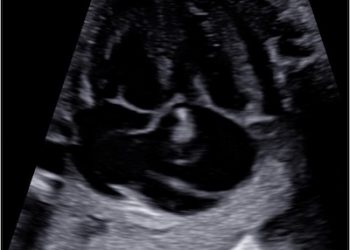

Per il mese di Dicembre SIEOG Giovani presenta il Webinar sullo screening delle cardiopatie congenite nel primo trimestre. La registrazione...